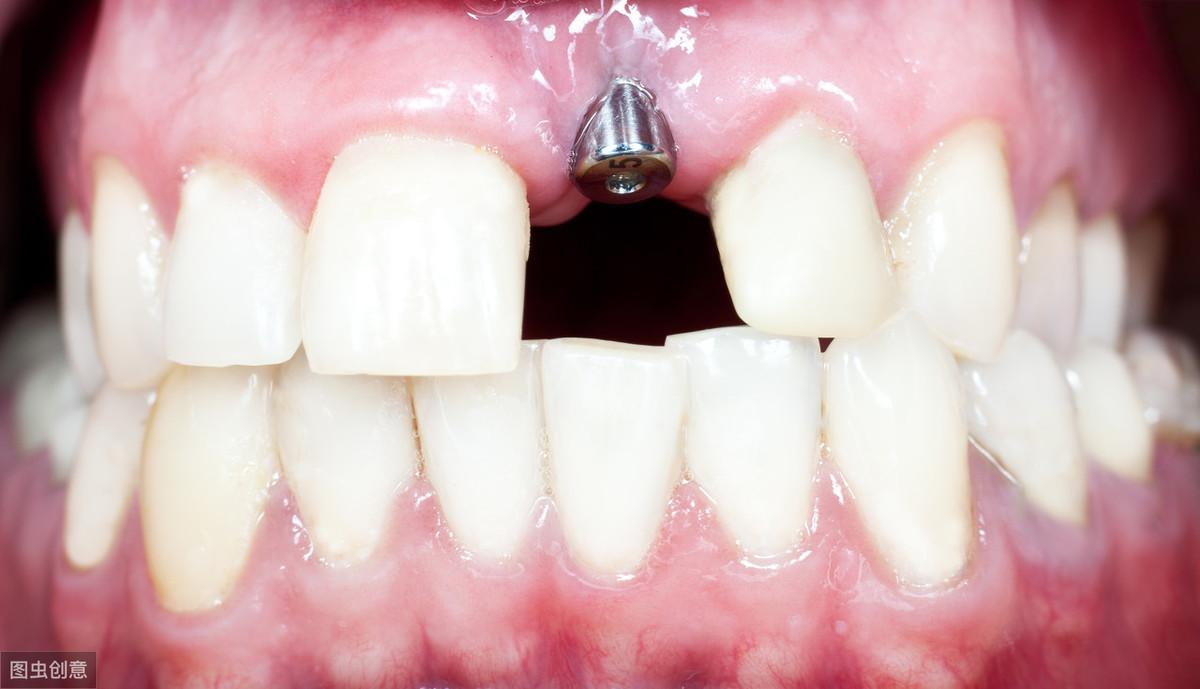

種植牙手術(shù)示意圖

種植牙技術(shù)是近幾十年出現(xiàn)在大眾視野中的一種修復(fù)缺失牙體的方法。一顆完整的種植牙體由三部分組成:種植體、基臺、人工牙冠。

手術(shù)過程就是將種植體植入患者的牙體缺失處,待其傷口愈合,種植體與牙槽骨結(jié)合牢固后,將基臺安裝在種植體上,再將人工牙冠安裝在基臺上,形成完整而堅固的人工牙體。

種植牙技術(shù)就像在缺失牙體處種一顆新的牙齒,能夠和牙槽骨結(jié)合,做種植牙能有預(yù)防牙槽骨萎縮,這是普通的假牙無法做到的,而且種植牙體不依附周圍鄰牙,對鄰牙不造成任何負擔(dān),所以相對其他修復(fù)手段,不僅更為牢固不易松動,且使用壽命長,果好。